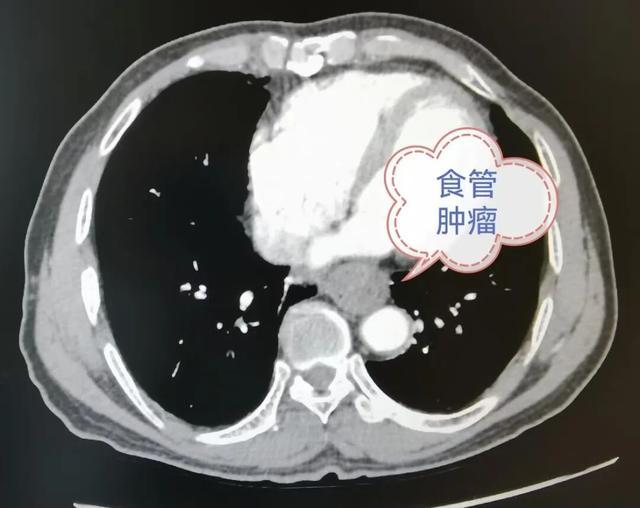

为吴先生完成相关检查后,胸外科邀请消化内科、普通外科二病区、医学影像科、麻醉手术科、血液肿瘤科等多学科专家会诊。专家们仔细分析检查报告,认为患者肿瘤尚未扩散,具备手术指征。

多学科团队经过缜密评估,决定采用胸腔镜联合腹腔镜的微创术式实施食管癌根治手术。